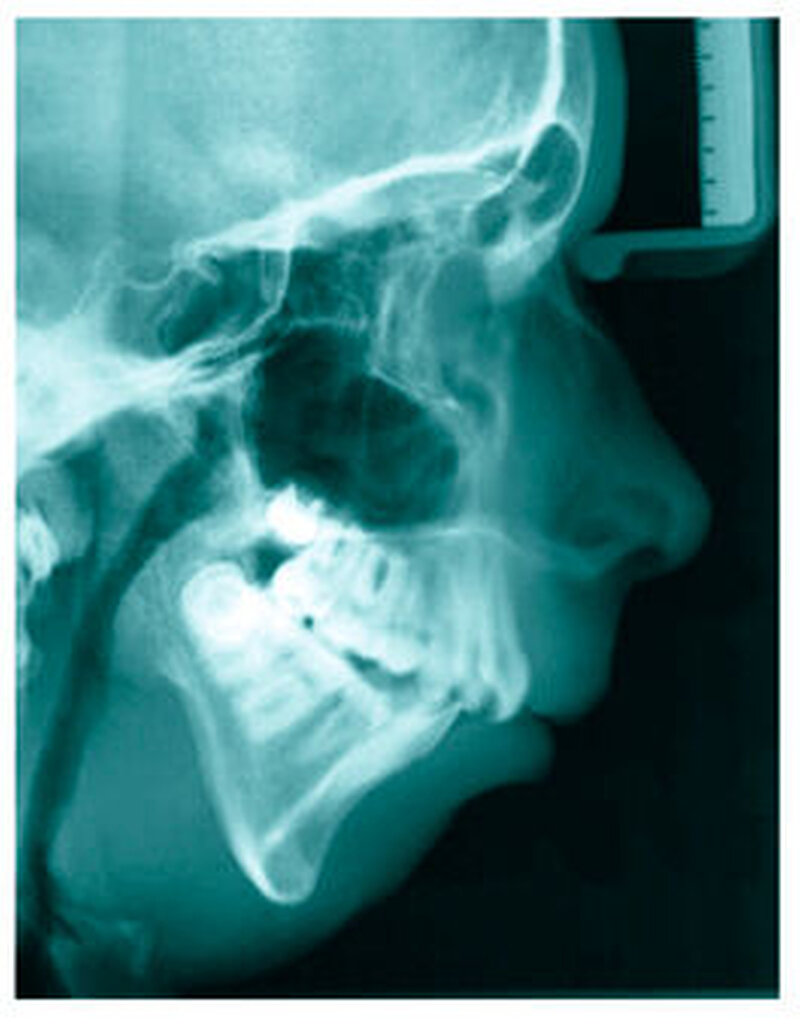

Bereits 2004 wies Carla Evans [Evans, 2005] auf das Risikomanagement bei Allgemeinerkrankungen hin und stellte am Beispiel der JIA dar, dass Unterkieferrücklagen und frontal offene Bisse aus der Kiefergelenkzerstörung entstehen können. Die Röntgenaufnahmen einer JIA-Patientin mit oligoartikulärer Form und Beteiligung des rechten Kiefergelenkes zeigen den typischen Verlauf sehr gut. Bei ursprünglich sehr dezenten Befunden, wie einer s-förmigen Mundöffnung von 44 mm, einer geringen Mittenabweichung um 2 mm nach rechts und einem frontal offenem Biss klagte sie über Schmerzen beim Essen, was den Anlass zur weiteren Diagnostik bot. Die erste Panoramaröntgenschichtaufnahme (Abbildung 1a-c) zeigt auf der rechten Seite einen abgeflachten Kondylus und eine bereits verstrichene Fossa condylaris. Ein Jahr später vermittelt das Fernröntgenseitenbild (Abbildung 1d) trotz fortschreitender kondylärer Resorption ein harmonisches Bild, während nach drei Jahren bei voranschreitendem Abbau des rechten Kondylus (Abbildung 1e) eine Rücklage der Mandibula und eine Bissöffnung manifest sind (Abbildung 1f).

Die Fernröntgenseitenaufnahme in Abbildung 2a zeigt ein „rheumatisches“ Profil mit retraler, hypoplastischer Mandibula, oft kombiniert mit einer Schwäche des M. masseter auf der betroffenen Seite. Der Funktionsschmerz erzeugt „Kaufaulheit“. Die Gesichtsasymmetrie (Abbildung 2b) betrifft meist Kinn, aufsteigenden Ast und die Höhe der Kieferwinkel. Auch die nicht dentoalveoläre Mittellinienverschiebung kann auf eine JIA hinweisen. Kreuzbisse variieren in Abhängigkeit vom Grad der Unterkiefermittenabweichung. Gemeinsame Auftreten eines frontal offenen Bisses und eines vergrößerten Overjet sind als klinische Anzeichen zu bewerten.